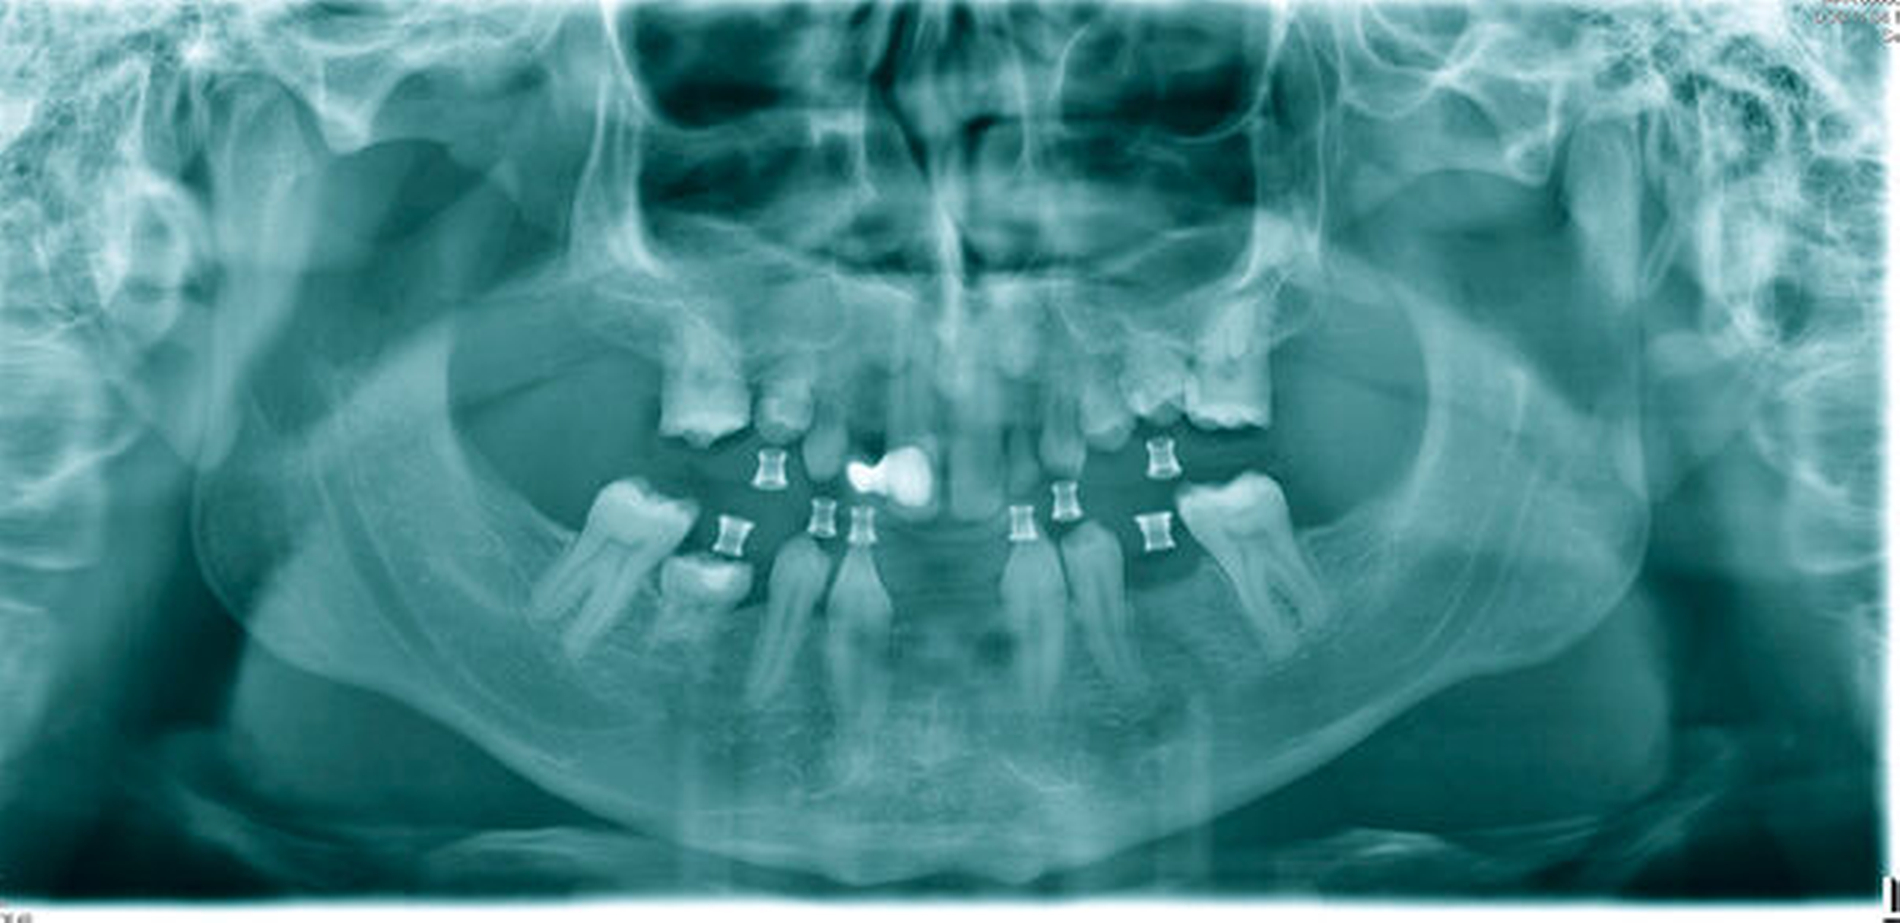

Beim intraoralen Befund imponierten neben multiplen Lücken ein partiell seitlich-offener Biss, eine auffällig konische Form der oberen mittleren Schneidezähne sowie persistierende Milchzähne (Abbildungen 2 bis 4). Zusammen mit der angefertigten Panoramaschichtaufnahme (Abbildung 5) konnte der Verdacht einer ausgeprägten Oligodontie bestätigt werden – insgesamt waren 22 Zähne inklusive der Weisheitszähne nicht angelegt. Auf Grundlage der bestehenden Befunde wurde der Verdacht einer genetischen Ursache der Symptome geäußert und dem Patienten zunächst eine molekulargenetische Abklärung mit der Verdachtsdiagnose „genetisch bedingte Zahnnichtanlagen / ektodermale Dysplasie“ empfohlen. Bei der Sequenzanalyse wurde eine Mutation im WNT10A-Gen nachgewiesen und somit die klinische Verdachtsdiagnose bestätigt.